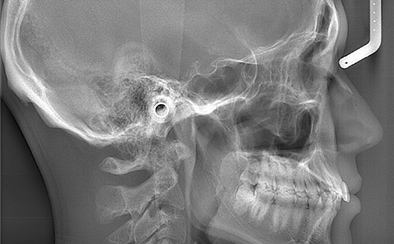

小児矯正において、お子さんの口周りの状態をしっかりと確認して治療計画に盛り込むことは重要です。当院では治療前の精密検査が可能であり、歯科用CT、口腔内3Dスキャナー(iTero)、セファロなどの先端機器を使用いたします。精度の高い検査と治療を行いますでご安心ください。

セファロ